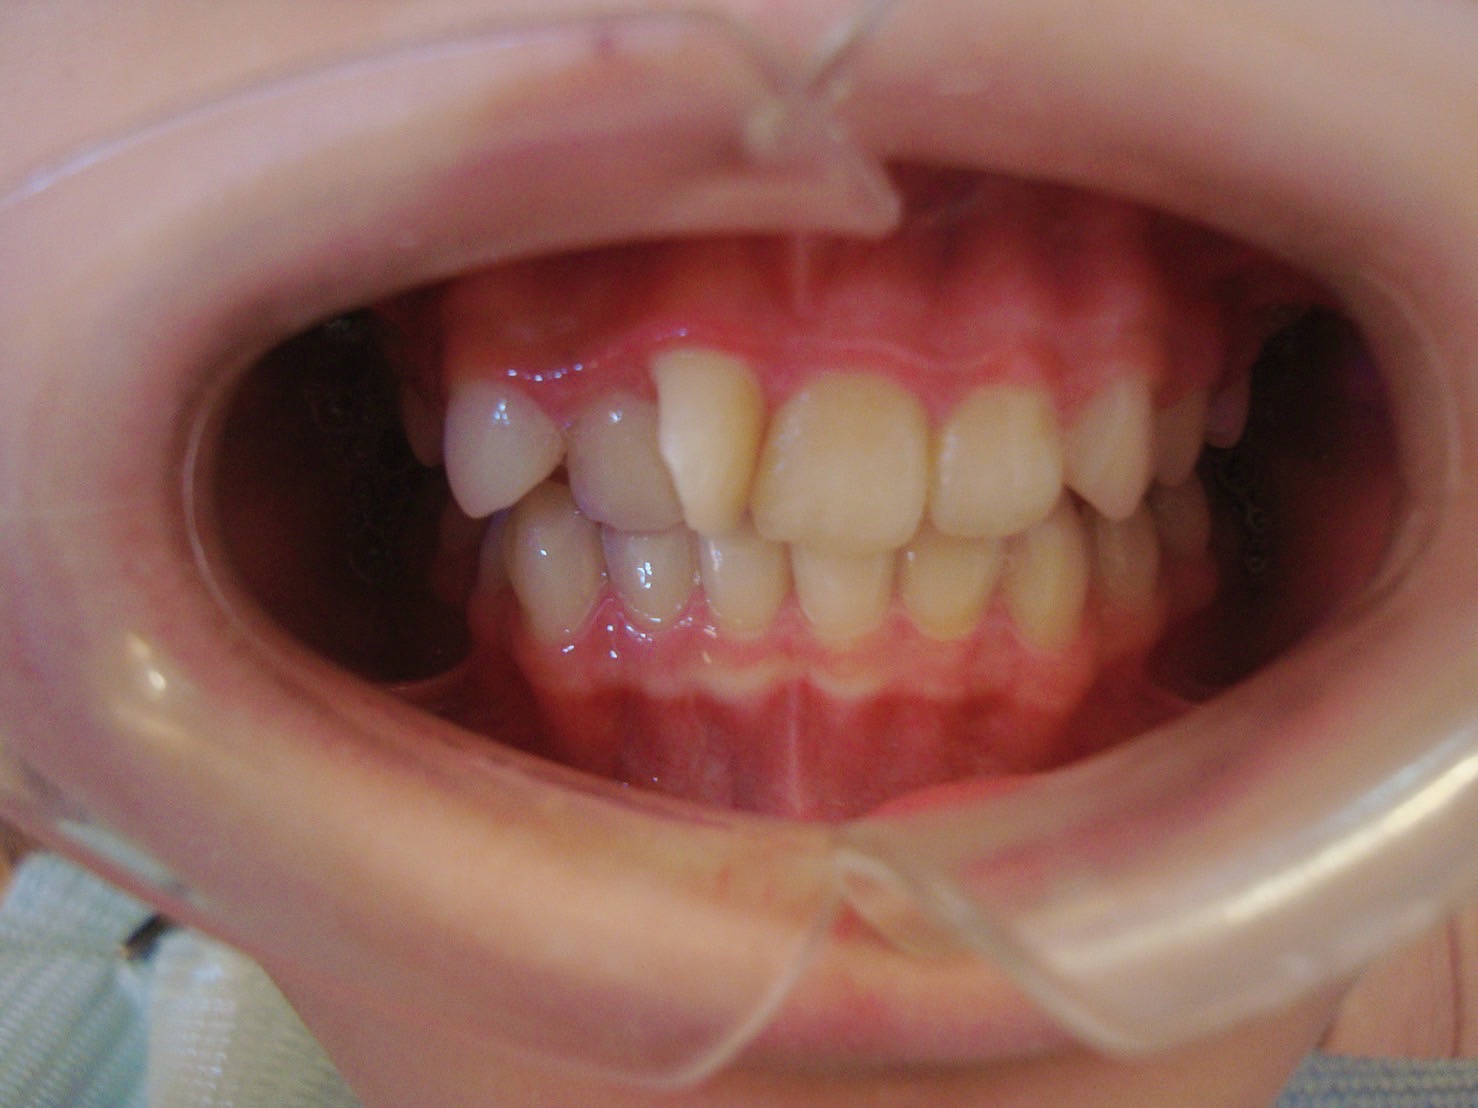

牙齒矯正